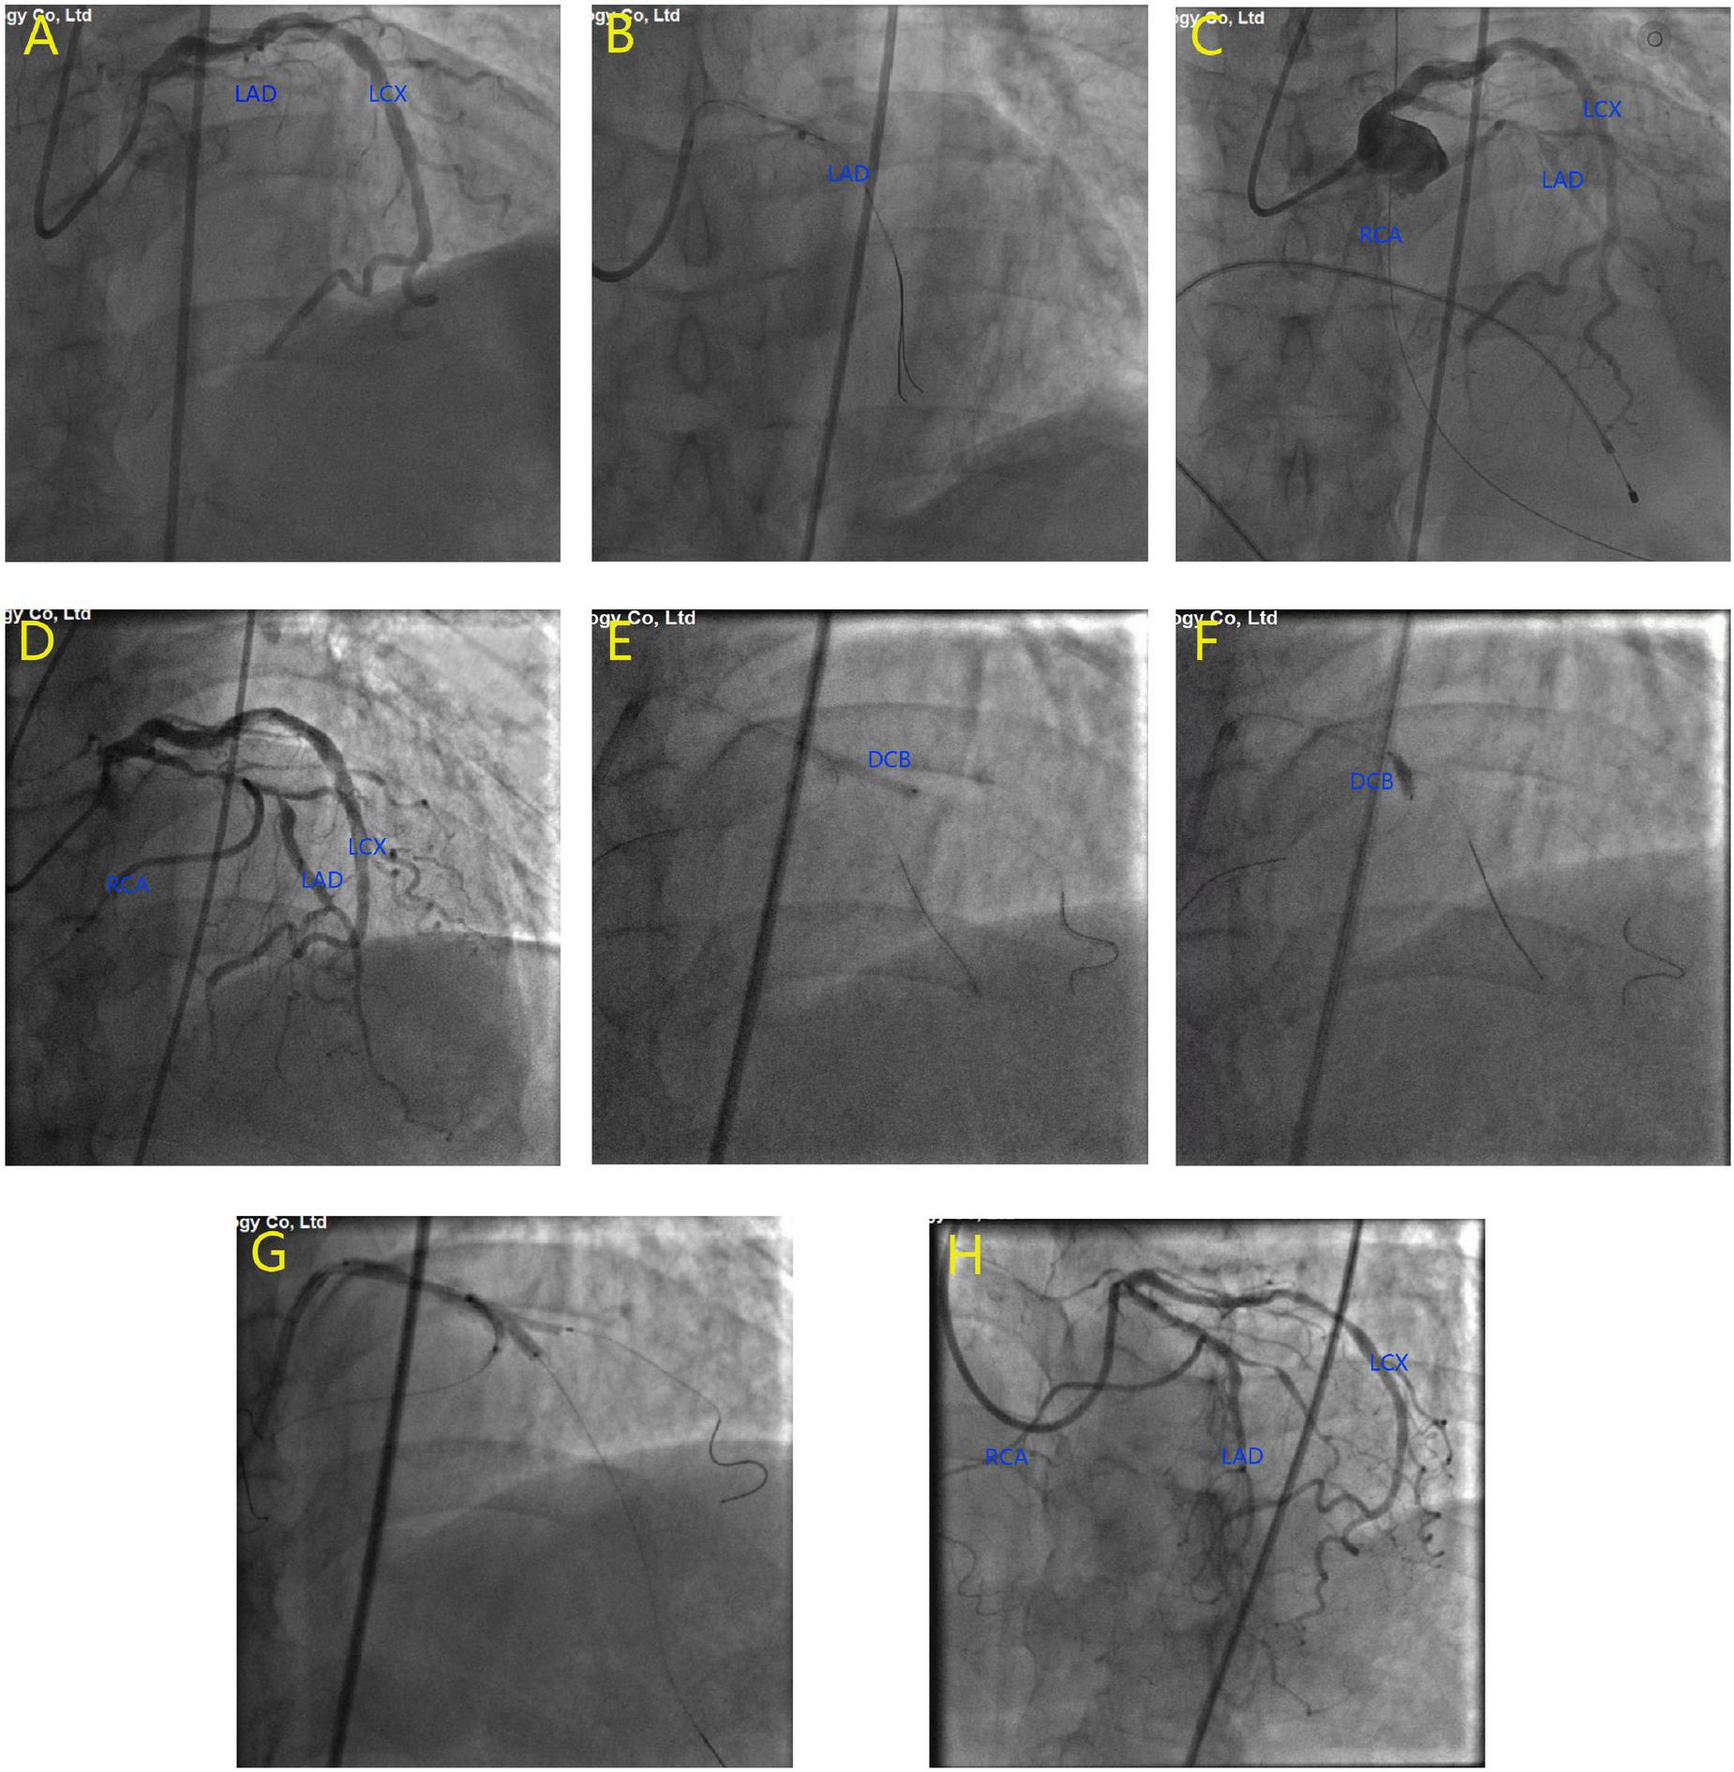

FIGURE 2

Emergency coronary angiography at the onset of acute myocardial infarction. The results showed that the proximal left anterior descending artery (LAD) was completely occluded (A). Balloon dilatation was performed on the occlusive site (B). TIMI grade 3 flow was restored in LAD and right coronary artery (RCA) (C). The second coronary angiography at 4 months after myocardial infarction. The results showed high-grade lesion at the proximal LAD, as well as at LAD/RCA bifurcation and LAD/diagonal bifurcation (D). Drug-eluting balloons were used to dilate the diagonal branch (E) and the RCA (F). A drug-eluting stent in LAD and 2 balloons in D1 and RCA were dilated simultaneously for kissing balloon inflation (G). Final imaging results after procedure (H).

With the aid of IABP, a guide wire was used to cross the occluding lesion of the LAD, and TIMI grade 3 blood flow was achieved after balloon angioplasty. We found that the left circumflex is the dominant artery and RCA originated from the middle of the LAD (Figures 2B, C). As the ECG monitor showed a ventricular rate of 36 and iii° AV block occurred, we performed a temporary pacemaker. Due to massive thrombosis in the coronary arteries and unstable vital signs, we decided to stop the operation and initiate intensive antithrombotic therapy. After 2 weeks of therapy, the patient’s vital signs stabilized, his chest pain disappeared, and his heart failure improved. We gradually removed the IABP, temporary pacemaker, and vasopressors. Then, coronary artery bypass surgery (CABG) or re-percutaneous coronary intervention (PCI) was recommended for the patient, but he and his family rejected this recommendation.

Four months after discharge, the patient was advised again to undergo coronary angiography, and the results showed complex and severe triple bifurcated lesions, with 90% ostial LAD lesions, 80% ostial D1 lesions, and 70% ostial RCA lesions (Figure 2D). Following coronary angiography, we discussed the revascularization strategy. Two Sion blue wires were passed down the LAD, D1, and anomalous RCA, and two 2.5 × 20 mm drug-coated balloons were deployed in the D1 and RCA (Figures 2E, F). Then, the LAD/RCA/D1 bifurcation was treated with a 3.0 × 36 mm (10 atm) drug-eluting stent (DES) placed in the LAD and two Maverick 2.0 × 20 mm (6 atm) balloons placed in the D1 and RCA (Figure 2G), which were dilated simultaneously for kissing balloon inflation. Then, a proximal optimization technique (POT) was performed with a Quantum Maverick 3.0 × 15 mm high-pressure balloon placed in the LAD. With no symptoms of discomfort, PCI was completed, and the outcomes were satisfactory (Figure 2H). After 3 days, the patient was discharged home on aspirin, ticagrelor, and rosuvastatin. After a 1-month follow-up, we performed computed tomography angiography (CTA) of the coronary artery. Through CTA, we confirmed that the anomalous RCA originated from the middle of the LAD (Figure 3). It passed between the aorta and pulmonary artery in the group of L-II variants (1).